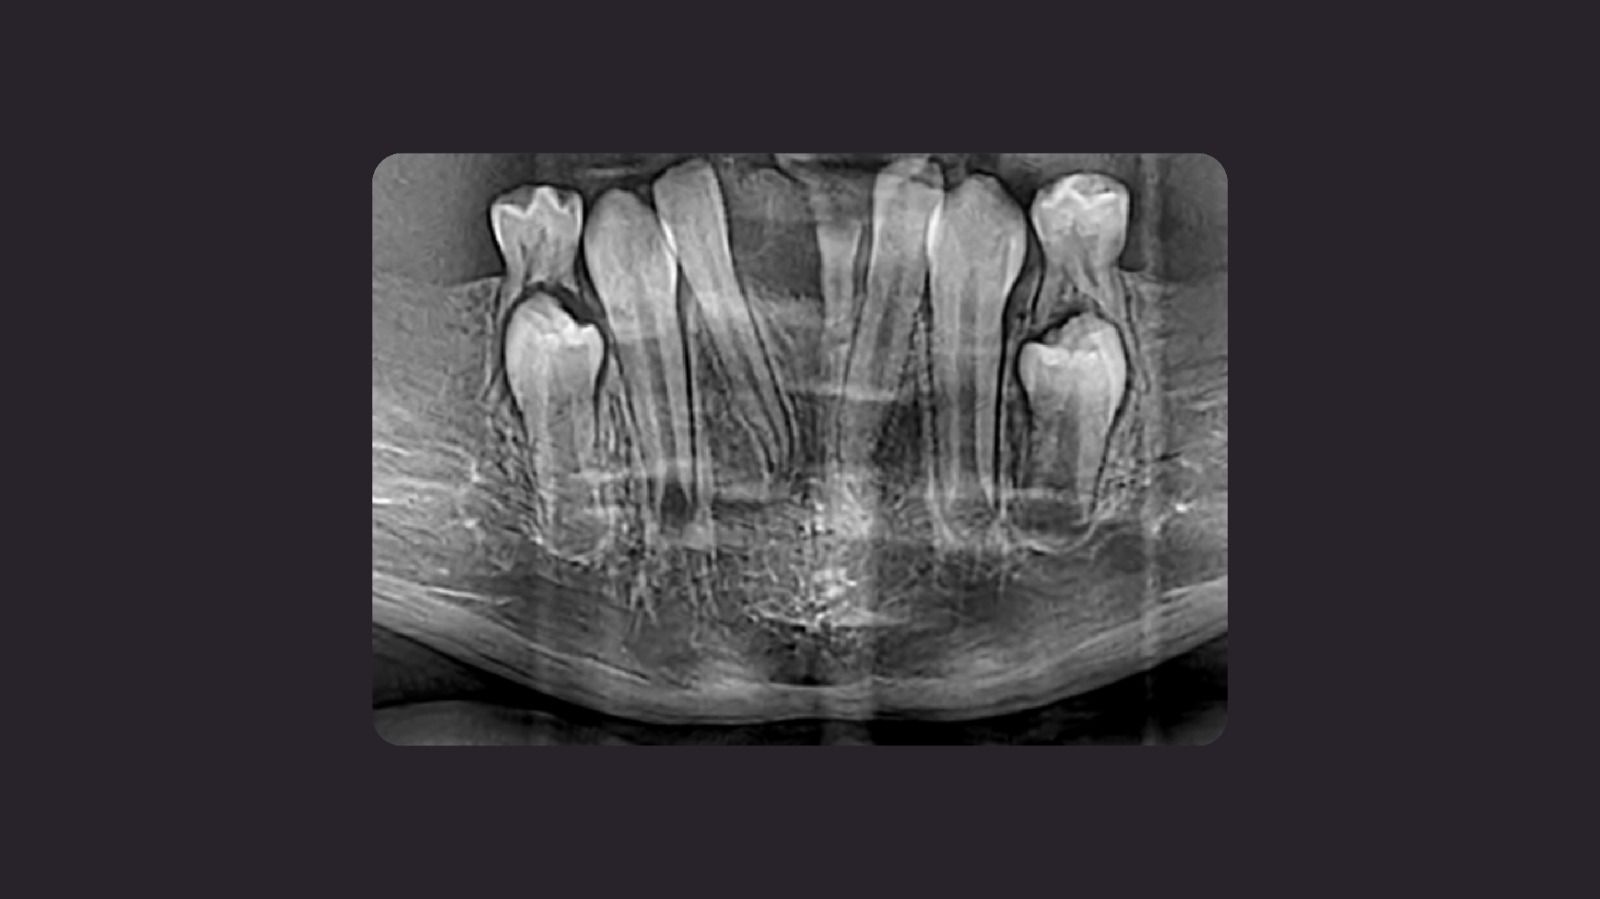

Figura 1

Fig.1: Radiografía panorámica. Al examen radiográfico se constató:

- Dentición mixta. Anodoncia parcial con ausencia de múltiples piezas dentarias involucrando dentición temporal y definitiva compatible con Oligodoncia.

- Agenesia de molares y segundos premolares permanentes en el maxilar superior e inferior.

- Múltiples giro versiones.

- Rebordes alveolares reducidos con reabsorción de procesos alveolares en el maxilar superior y presencia de diastemas.

En base en las características radiográficas se propuso el diagnostico diferencial de Displasia Ectodérmica.